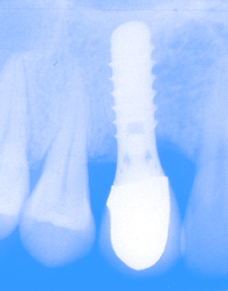

Info on Dental Implants A Dental Implant is a small titanium screw that acts as a replacement for the missing root of a tooth. After the screw has had time to integrate into the bone over a period of months, the dental implant will then act as the foundation for a crown. Dental Implants are an excellent option for replacing single or multiple teeth.. |